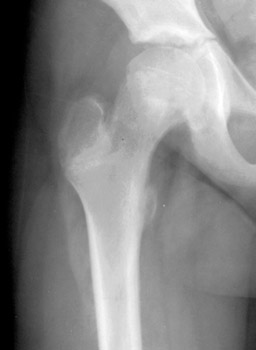

Skeletal Trauma > Pelvis & Hips > Slipped Femoral Epiphysis

Slipped Femoral Epiphysis

| Slipped Femoral Epiphysis | Slipped Femoral Epiphysis Reset | |